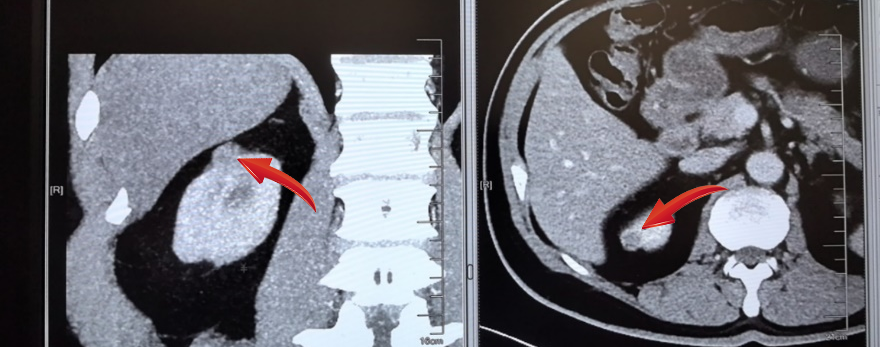

近期,55岁的王女士,因“胃脘胀痛半年” 入院,本来打算看个胃病,结果火眼金睛的放射科医生在其腹部增强CT中看出“端倪”:右肾下极占位(弱强化灶),大小:9.5mm,考虑MT可能,遂立即转入泌尿外科,排除手术禁忌证后在全麻下行“腹腔镜下肾部分切除术”,手术顺利,术后恢复良好。病理显示:透明细胞性肾细胞癌。

无独有偶,62岁的金先生,在放射科诊查泌尿系平扫+增强CT+CTU中:患者右肾上极肿块,囊实性,包膜完整,直径约1.5cm肿瘤,与周围少粘连;入院后完善术前检查,排除手术禁忌证后在全麻下行“腹腔镜下肾部分切除术”,手术顺利,术后恢复良好。病理显示:透明细胞性肾细胞癌。

泌尿外科张曦医生介绍,手术过程简洁但不简单:病人采取全身麻醉,麻醉成功后摆术中侧卧位,于患侧腰部取三个长约1.5cm的微创切口,进入微创手术器械,小心分离,显露出患侧肾脏,因此类患者肿瘤较小,术中为确认肿瘤位置及边界,还需借助一利器,即术中B超,大大帮助医生进一步确认肿瘤位置大小,降低手术风险,将肿瘤完整切除。手术后患者将在专业团队的帮助下进行术后恢复。